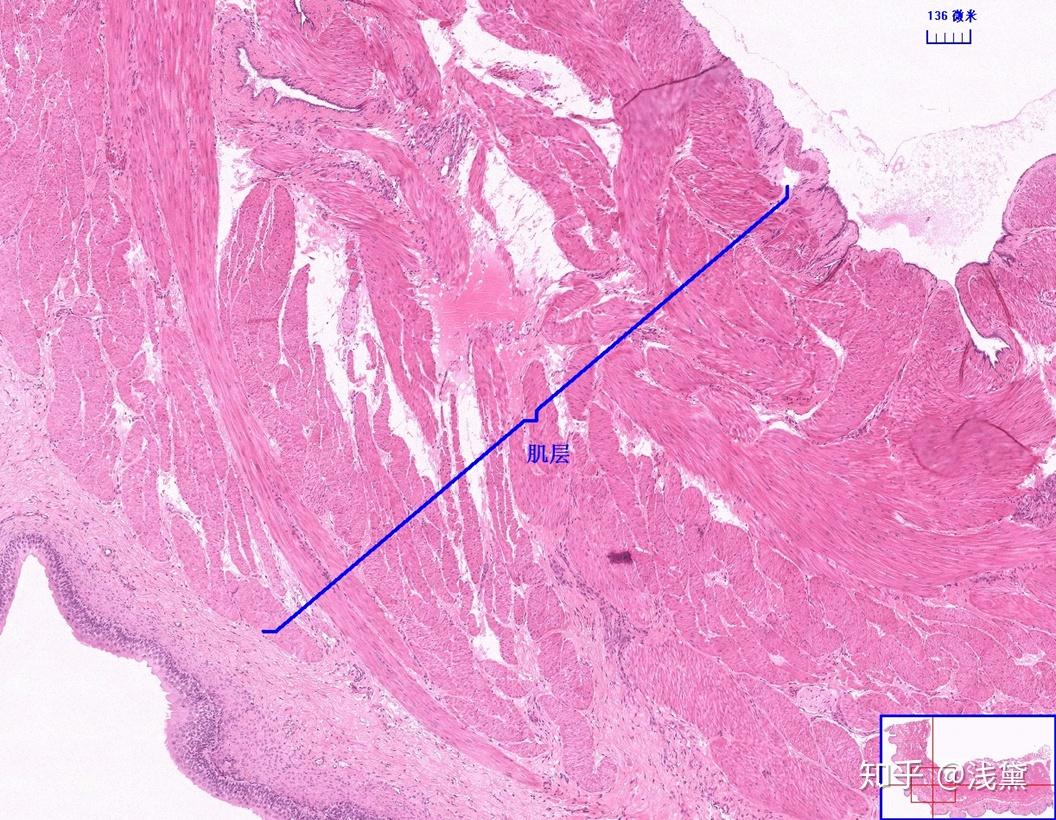

甲状腺滤泡癌切片